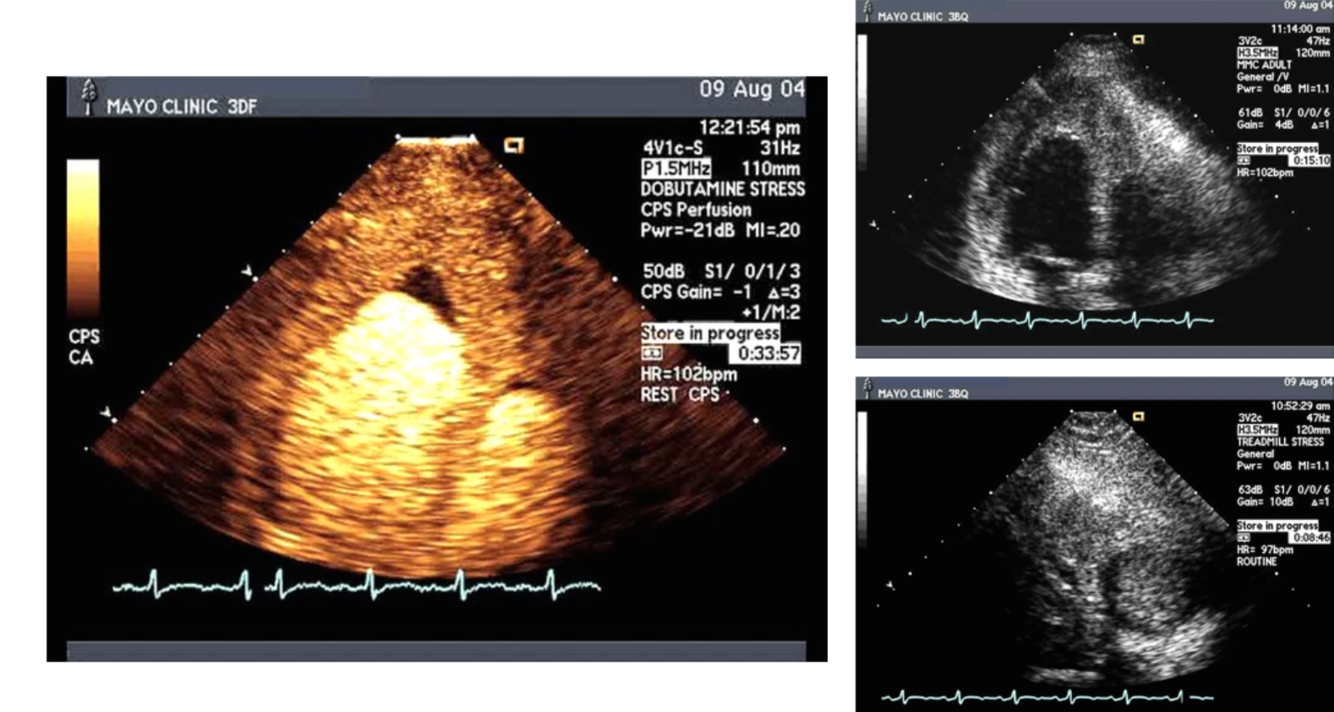

Diagnosis? next step?

Hypereosinopilic Syndrome (inflammation–> thrombosis–> fibrosis), check CBC w/ dif.